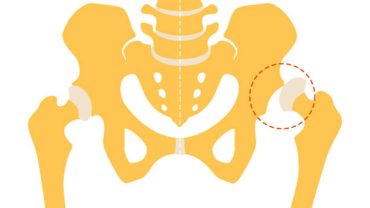

Bebeklerin kalça ekleminin normal gelişimini engelleyen bir durumdur. Bebeklerde doğuştan olabilir veya doğum sonrası ilk aylarda ortaya çıkabilir. Erken teşhis ve gelişimsel kalça displazisi tedavisi…

Bebeklerin kalça ekleminin normal gelişimini engelleyen bir durumdur. Bebeklerde doğuştan olabilir veya doğum sonrası ilk aylarda ortaya çıkabilir. Erken teşhis ve gelişimsel kalça displazisi tedavisi…

Femur başında dolaşım bozukluğu nedeniyle meydana gelen bir durumdur. Bu durumda, kemik dokusu yeterli kan akışını alamaz ve zamanla ölür. Kalça eklemi ile ilişkili olan…

Kalça eklemindeki labrum adı verilen kıkırdaklı dokunun yırtılması durumudur. Bu doku, kalça eklemi kemiği ve pelvik kemik (acetabulum) arasındaki eklem kapsülünü kaplayan halka şeklindeki bir…

Bebeklerin kalça ekleminin normal pozisyonundan çıkmış olması durumunu ifade eder. Doğuştan kalça çıkığı, kalça eklemi ve pelvisin normal gelişimini engeller. Bebeklerde fark edilmeyebilir ancak ilerleyen…